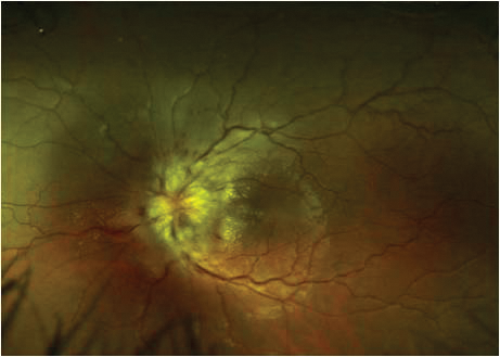

A 30-year-old Caucasian presented with the first episode of unilateral, painless visual loss in one eye upon waking. Crohn’s disease was diagnosed 18 months ago on colonoscopy after a single episode of colitis. She was on no medication. She presented with gross swelling of the optic nerve head on the right and swelling of the left optic nerve head. Vision was 6/36 on the right and 6/9 on the left.

Figure 1 (top and above): Case 2 - right and left fundus.

There was a dense right RAPD, reduction in colour vision, a large, dense unilateral, nasal scotoma, and bilateral mild vitritis. MRI showed no white matter lesions. She was treated with high dose oral steroids with a residual dense nasal field defect and central visual acuity of 6/9. This is an atypical optic neuritis which may be associated with Crohn’s disease. Here the atypical features are the absence of pain, gross optic nerve head swelling and bilateral disease. The presence of intermediate uveitis is consistent with Crohn’s disease. The MRI findings support the likelihood that this pathological process was limited to optic nerve.